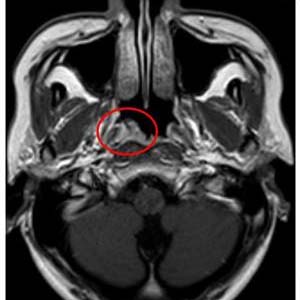

2.病毒感染:比較典型的就是EB病毒、冠狀病毒感染等,這些病毒會參與到鼻咽癌的發展過程當中,也就是說發生病毒感染未及時治療,也可能導致鼻咽癌問題。是一種常見的惡性腫瘤,其發生范圍很廣,比如80%以上的鼻咽癌患者在次檢測到淋巴結轉移。

隨著病情的發展,還會表現出與之相對應的臨床表現,比如:鼻咽癌會有回吸涕帶血,嚴重時會影響到顱神經,比如頭痛、上瞼下垂等,還會導致軟腭癱瘓,聲音嘶啞,伸舌偏斜等。鎳元素可促進亞硝胺誘發鼻咽癌,酒精和煙草、維生素缺乏、性激素失調都增加黏膜對致癌物的敏感性。